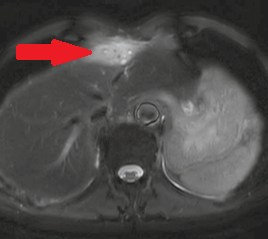

Αξονική τομογραφία κοιλίας – Θρόμβωση αριστερού κλάδου πυλαίας φλέβας. Ευγενική παραχώρηση Dr. V. Penopoulos.